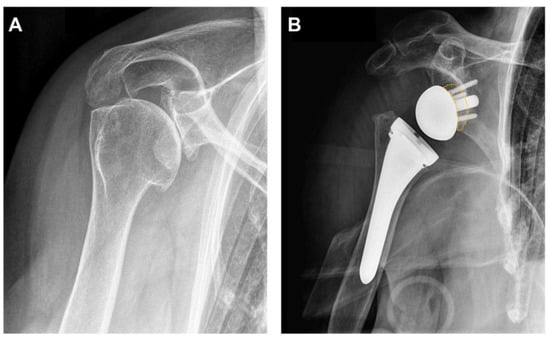

2. Biomechanical Considerations

3.3. Humeral Component